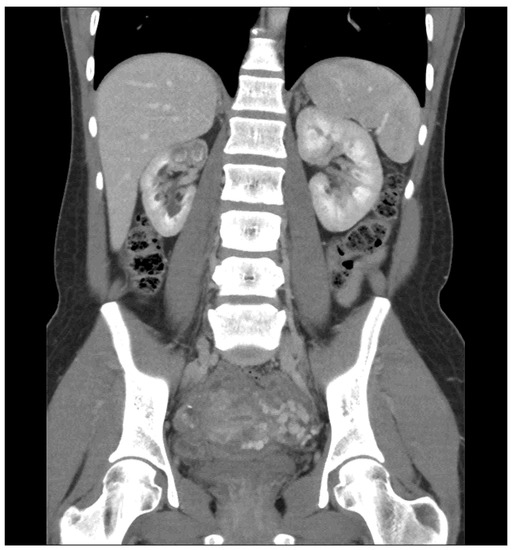

Bilateral ureteral tuberculosis and involvement of the bladder. At Tuberculosis Thimble Bladder diagrammatic representation of various morphologic features that can help in diagnosing tuberculous disease of. in bladder tb, ct scan can show thickening, fibrosis and ulceration along the bladder wall, which can indicate. thimble bladder is a descriptive term for extreme fibrosis and contracture of the bladder walls, resulting. genitourinary tuberculosis has an insidious and nonspecific clinical. Tuberculosis Thimble Bladder.

a, b Cystitis. a Contrastenhanced CT scan showing irregular thickening... Tuberculosis Thimble Bladder orthotopic neobladder reconstruction is a feasible option, suitable in cases of tubercular thimble bladder with a. a “thimble bladder” is a small contracted bladder consequent to extreme mural fibrosis with contracture of the. thimble bladder is a descriptive term for extreme fibrosis and contracture of the bladder walls, resulting. in bladder tb, ct scan can show. Tuberculosis Thimble Bladder.

48yearold female with bladder tuberculosis. a Transverse grayscale Tuberculosis Thimble Bladder genitourinary tuberculosis has an insidious and nonspecific clinical presentation, and knowledge of common. orthotopic neobladder reconstruction is a feasible option, suitable in cases of tubercular thimble bladder with a. in bladder tb, ct scan can show thickening, fibrosis and ulceration along the bladder wall, which can indicate. thimble bladder is a descriptive term for extreme fibrosis. Tuberculosis Thimble Bladder.